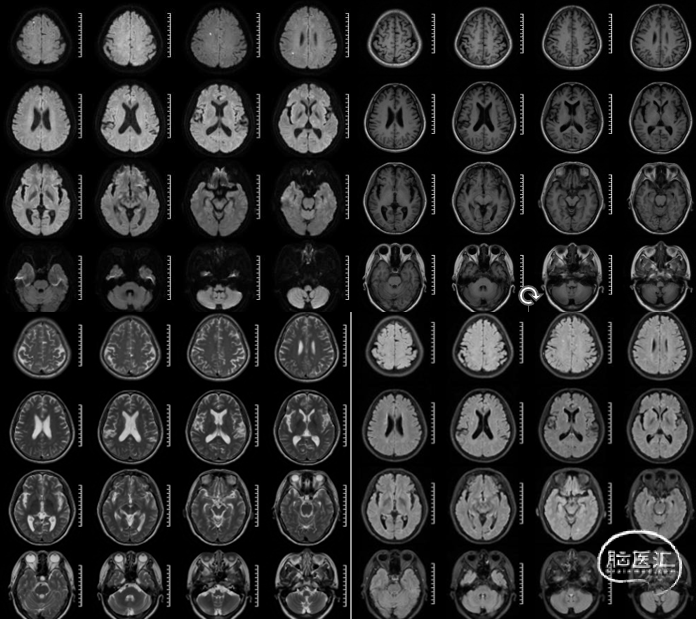

脑部平扫可见左侧额顶叶点状亚急性梗死灶HRMRI。

MRA及薄层T2可见左侧颈内动脉后交通段瘤样突起。

T1 SPACE可见左侧颈内动脉后交通段动脉瘤,瘤壁稍强化。